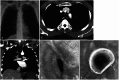

Purpose: Tracheal restenosis due to excessive granulation tissue around a silicone stent requires repeated bronchoscopic interventions in patients with post-tuberculosis tracheal stenosis (PTTS). The current study was conducted to identify the risk factors for granulation tissue formation after silicone stenting in PTTS patients.

Materials and methods: A retrospective study was conducted between January 1998 and December 2010. Forty-two PTTS patients with silicone stenting were selected. Clinical and radiological variables were retrospectively collected and analyzed.

Results: Tracheal restenosis due to granulation tissue formation were found in 20 patients (47.6%), and repeated bronchoscopic interventions were conducted. In multivariate analysis, tracheal wall thickness, measured on axial computed tomography scan, was independently associated with granulation tissue formation after silicone stenting. Furthermore, the degree of tracheal wall thickness was well correlated with the degree of granulation tissue formation.

Conclusion: Tracheal wall thickening was associated with granulation tissue formation around silicone stents in patients with post-tuberculosis tracheal stenosis.